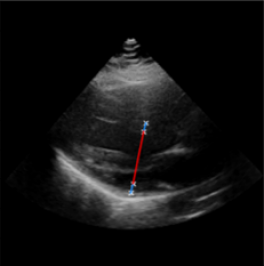

Left Ventricular Hypertrophy (LVH), one of the leading predictors of adverse cardiovascular outcomes, is the condition where heart’s mass abnormally increases secondary to anatomical changes in the Left Ventricle (LV) [10]. These anatomical changes include an increase in the septal and LV wall thickness, and the enlargement of the LV chamber. More specifically, Inter-Ventricular Septal (IVS), LV Posterior Wall (LVPW) and LV Internal Diameter (LVID) are assessed to investigate LVH and the risk of heart failure [21]. As shown in Figure 1 (a), four landmarks on a parasternal long axis (PLAX) echo frame can characterize IVS, LVPW and LVID, and allow cardiac function assessment. To automate this, machine learning-based (ML) landmark detection methods have gained traction.

It is difficult for such ML models to achieve high accuracy due to the sparsity of positive training signals (four or six) pertaining to the correct pixel locations. In an attempt to address this, previous works use 2D Gaussian distributions to smooth the ground truth landmarks of the LV [9, 13, 18]. However, as shown in Figure 1 (b), for LV landmark detection where landmarks are located at the wall boundaries (as illustrated by the dashed line), we argue that an isotropic Gaussian label smoothing approach confuses the model by being agnostic to the structural information of the echo frame and penalizing the model similarly whether the predictions are perpendicular or along the LV walls.